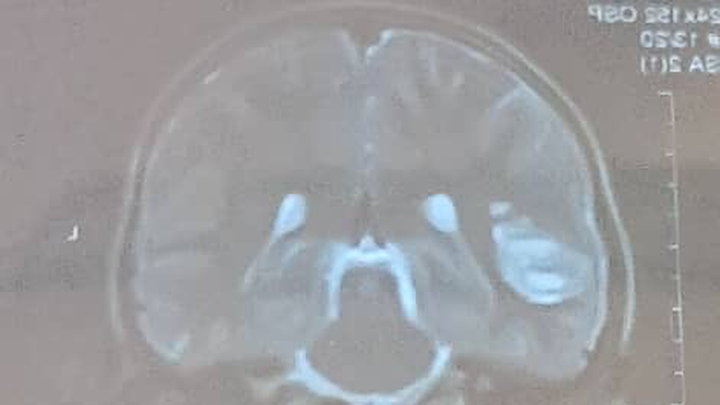

Hi my name is Rustam and I’m helping raise funds for my cousin in Afghanistan who is currently suffering from brain tissue damage.

He is only 13 years old and is the main breadwinner for his family, and he has 2 other sisters , a mother and a brother to look after.

Unfortunately, all the hospitals in Kabul has advised my cousin that he needs to travel to Pakistan or a foreign country to receive treatment, as they cannot treat it in Afghanistan due to the lack of specialists and resources in the country.